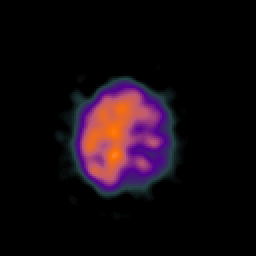

SPECT TC Study #6 -- Slice #45

[Home][Help][Clinical][Tour 1][Tour 2][Tour 3] Slice 45